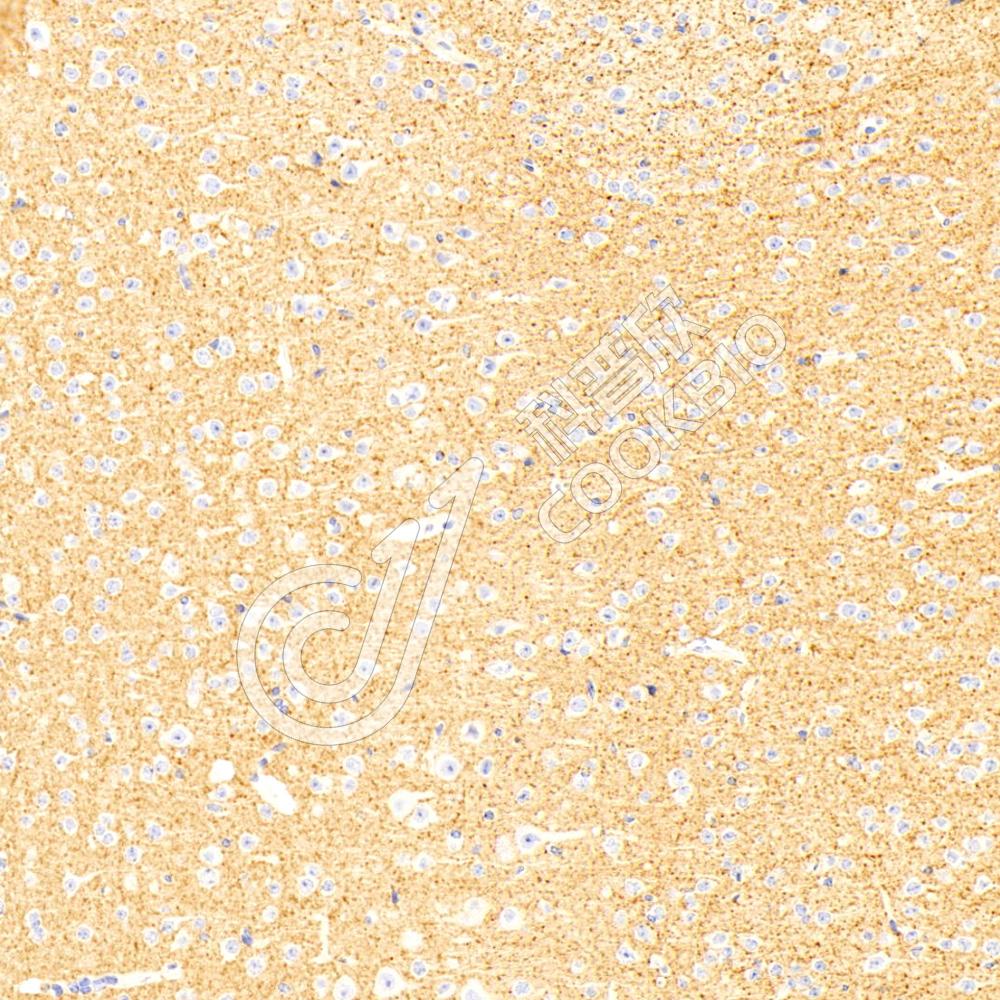

IHC检测GAP43蛋白(货号 K133285).

样品: 小鼠脑, 4%多聚甲醛 (货号KSG1101) 固定12-24小时.

抗原修复: 柠檬酸抗原修复液(干粉, pH 6.0) (KSG1201), 98℃, 20分钟.

—抗: 1: 600稀释, 4℃ 孵育过夜.

二抗: S-vision免疫组化多聚二抗(山羊抗兔),即用型 (货号KB3906), 室温孵育20分钟.